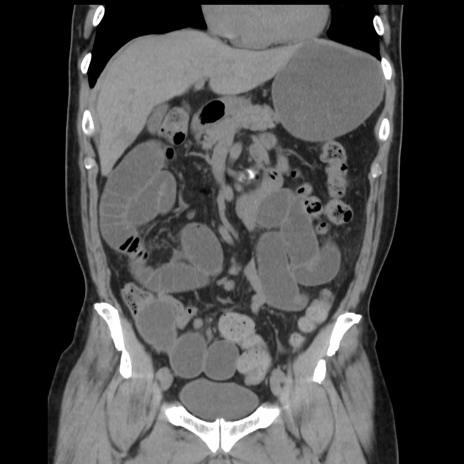

症例16(冠状断像)

【症例】 70歳代男性

【主訴】 腹痛、嘔吐

【現病歴】 約1ヶ月前より間欠的に腹痛と嘔吐あり、当院消化器内科を受診したところCTで多発する肝臓のLDAを指摘され、精査中であった。以降は消化器症状は安定していたが、2日前より嘔気と腹痛があり、同日より排便・排ガスが消失した。改善認めず、 本日、救急外来を受診した。

【既往歴】 大腸ポリープ切除後。

【身体所見】意識清明・会話良好、BT 36.3℃、BP 127/80mmHg、 P 80bpm、腹部:膨満あり、平坦・軟、上腹部正中および下腹部正中に圧痛あり、反跳痛なし、筋性防御なし。

【データ】WBC 7200、CRP 0.77